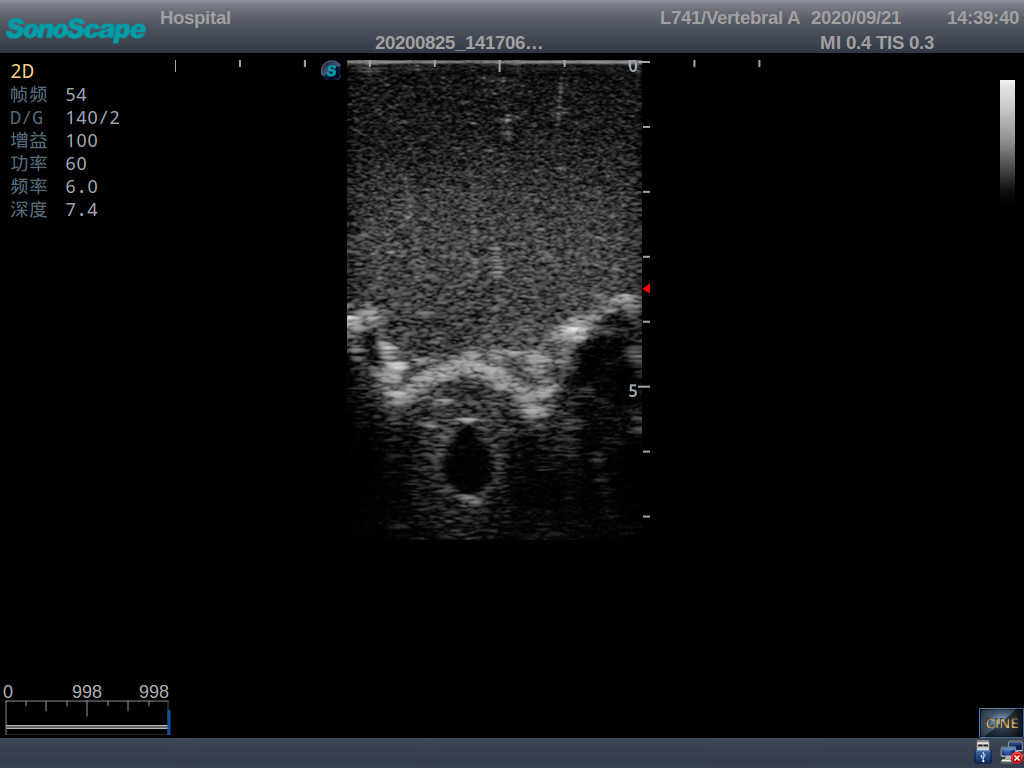

2) Real clinical ultrasound images

3) Compatible with various real ultrasound machines